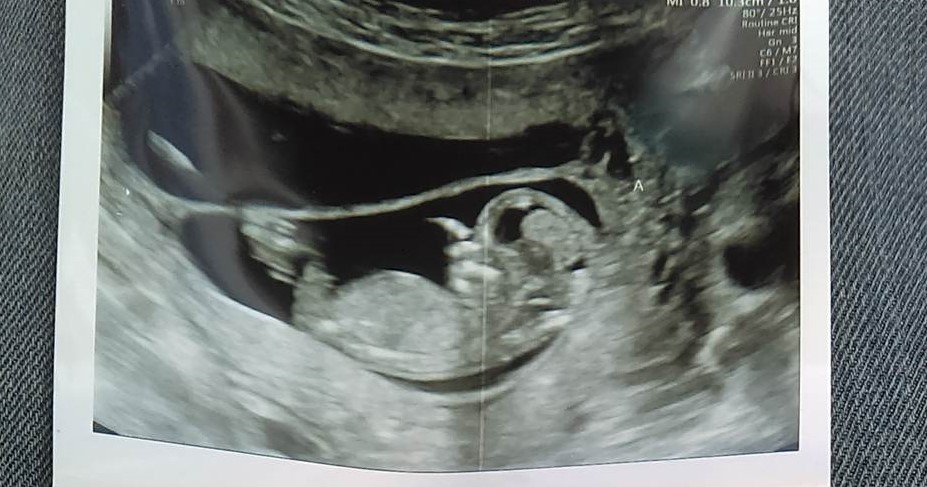

I had a private ultrasound down to find out the gender of my twins. the tech said they were measuring at 12 weeks 4 days so it was still early but she said baby a looks definitely like a girl and baby b she is unsure of but made an educated guess.....what do yall think?